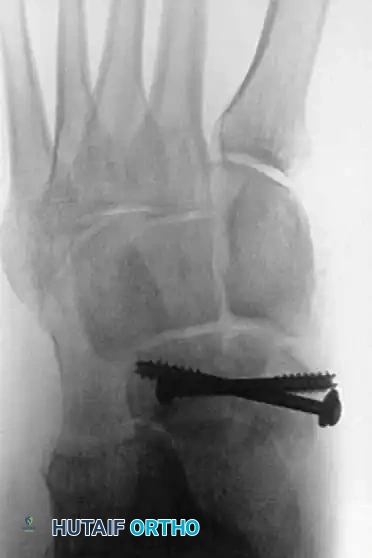

Fig. 86-36 Open reduction and internal fi xation of type III navicular fracture. A and B, Preoperative radiographs. C, Semicoronal CT scan showing comminution of body of navicular. D and E, Postoperative radiographs.

Fig. 86-36: Open reduction and internal fixation of a Type III navicular fracture. Note the severe comminution on the preoperative CT and the restoration of the medial column length postoperatively.